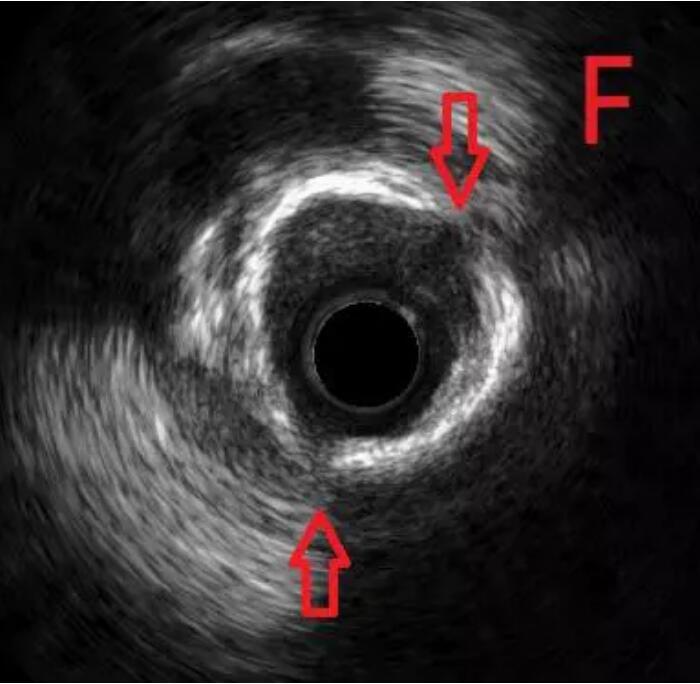

通过对该病变的分析,杨巍主任决定采用“振波球囊”对病变进行预处理。将振波球囊送至环形钙化处并启动4次,随后再次使用预扩球囊对病变处进行扩张,显示可以充分扩张(图E),继续IVUS检查,证实钙化斑块已经裂开(图F)。